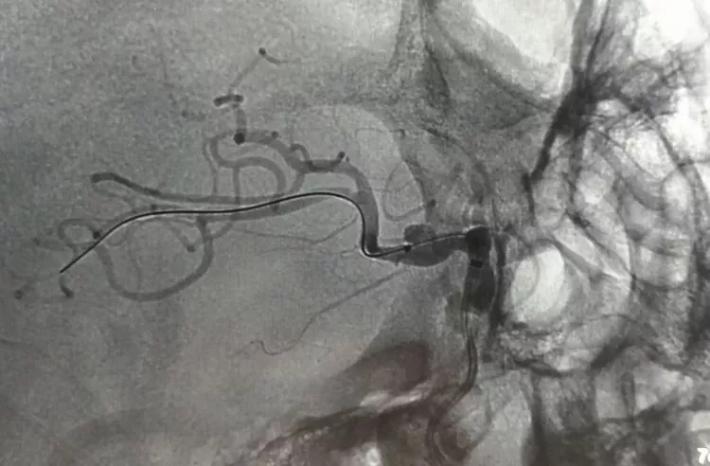

3D重建见BBA夹闭完全,脉前A(黄箭头)保留完好,局部颈内动脉通畅,桥血管通畅无吻合口狭窄(白箭头)!

超选ECA造影,STA→MCA桥通畅,MCA皮层支显影充分!

3D动态见BBA不显影,局部ICA管腔略窄,脉前A/STA→MCA吻合口通畅,手术达到预期效果,STA另支血管搭桥不需要了,关颅结束手术! 结论 术后CT未见MCA区域新发缺血,病人康复有望!